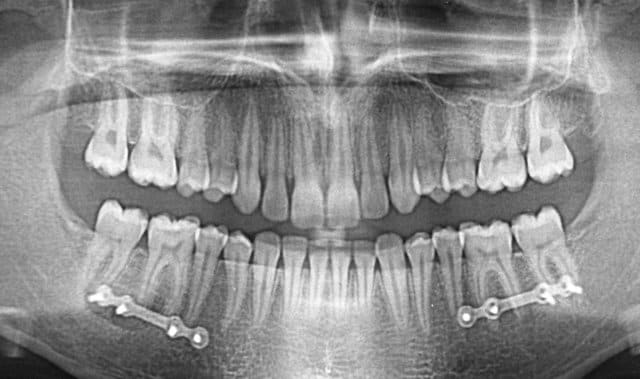

Cas extrême ? J’ai mieux que cela (fig. jointes).

Ami d’Eugénol qui lis ces lignes, rassure-toi ! Ce sont des cas de chirurgie maxillo-faciale qui n’ont rien à voir avec les cas d’ancrages osseux orthodontiques, ni avec la discussion en cours. Notre bon Bjc a introduit cet aparté car il aime bien les facéties.